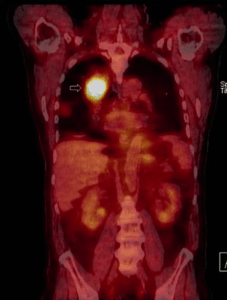

- Fluorodesossiglucosio F-18 (FDG): questo è di gran lunga il radiofarmaco più importante in oncologia. L’FDG è un analogo del glucosio che viene captato avidamente dalle cellule a alto metabolismo energetico, come le cellule tumorali maligne. La sua concentrazione all’interno delle cellule è un marker dell’attività metabolica e della proliferazione cellulare. La PET/TC con F-18 FDG è un pilastro nella diagnosi, stadiazione, valutazione della risposta alla terapia e nel follow-up di un’ampissima varietà di neoplasie.

La diagnosi e la caratterizzazione del tumore sono spesso il primo passo. Tecniche come la PET/TC con FDG sono preziose per determinare la natura maligna di una lesione sconosciuta (es. un nodulo polmonare solitario) e per la caratterizzazione fenotipica del tumore. La scintigrafia o la PET con recettori per la somatostatina è fondamentale per identificare e caratterizzare i tumori neuroendocrini.

La stadiazione iniziale e la ristadiazione rappresentano forse l’applicazione più consolidata. Determinare l’estensione della malattia (stadio) è cruciale per scegliere il trattamento più appropriato. La PET/TC con FDG, la PET con PSMA e altri radiofarmaci specifici sono insostituibili nell’individuare metastasi linfonodali e a distanza che potrebbero sfuggire alle metodiche di imaging convenzionale. Allo stesso modo, in caso di sospetta recidiva di malattia (ad esempio, un rialzo del PSA dopo un intervento per carcinoma prostatico), questi esami sono in grado di localizzare con precisione la sede della ripresa di malattia.